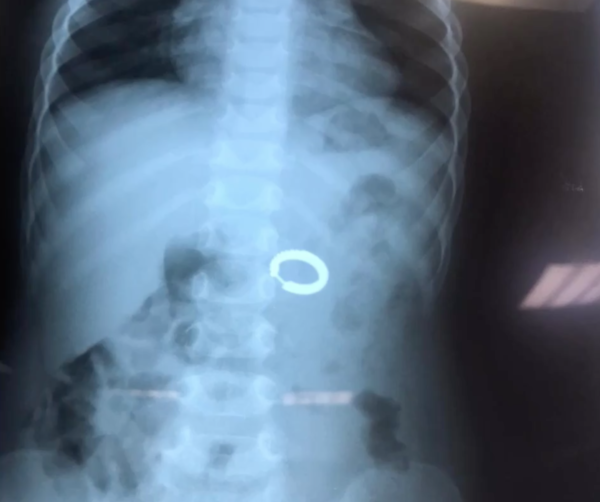

Рубрика «Интересный случай». Ребёнок, 1,5 года во время игры случайно подобрал с пола сережку и проглотил ее.

Ребёнок, 1,5 года во время игры случайно подобрал с пола сережку и проглотил ее, после чего стал попёрхиваться, кашлять, и плакать. Ребёнок в течении дня отказывался от еды и воды. Мама мальчика срочно вызвала скорую помощь. После проведённой предоперационной подготовки под наркозом инородное тело желудка удалено эндоскопически. ⠀ Мы надеемся, что демонстрация данного случая будет…